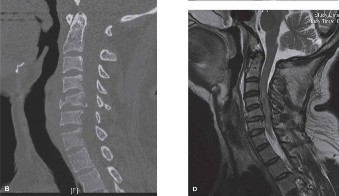

Pre-Operative Planning, Templating, and Patient Positioning

When surgical intervention becomes unavoidable, meticulous pre-operative planning is the cornerstone of a successful outcome. Advanced imaging is non-negotiable. An MRI with and without gadolinium contrast is the gold standard for defining the extent of the epidural abscess, the degree of neural compression, and the involvement of adjacent paraspinal musculature (e.g., psoas abscess). T1-weighted images typically show hypointense signals in the infected marrow, while T2-weighted and STIR sequences reveal hyperintense fluid and edema in the disc space and vertebral bodies. Gadolinium enhancement highlights the vascularized inflammatory phlegmon and the capsule of any abscesses.

In addition to MRI, a fine-cut computed tomography (CT) scan is essential for evaluating bony destruction. CT allows the surgeon to assess bone stock for pedicle screw purchase and to template the size of the interbody cages required for anterior column reconstruction. Upright standing radiographs (if the patient can tolerate them) or full-length supine films are necessary to evaluate global spinal alignment and regional kyphosis.